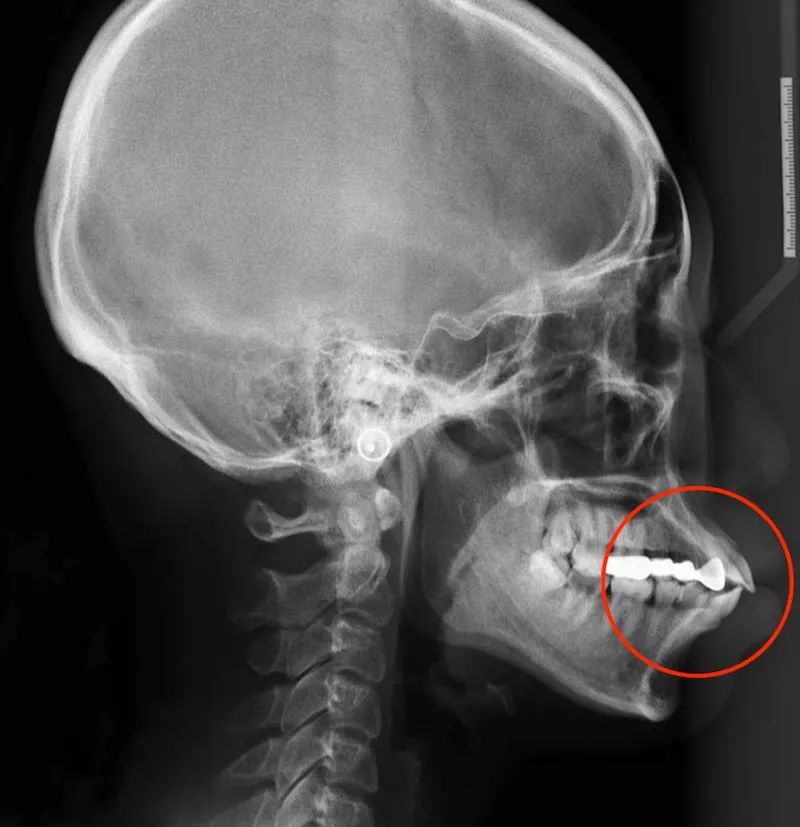

多牙症头颅

混合型的治疗方案,需要根据实际的牙齿情况以及头颅侧位片来定夺.

成人非手术拔牙正畸治疗,"再造"一个美丽的下巴头颅侧位片侧面面型

头颅侧位治疗前后对比曲断治疗前后对比前牙ct治疗前后对比关节ct治疗